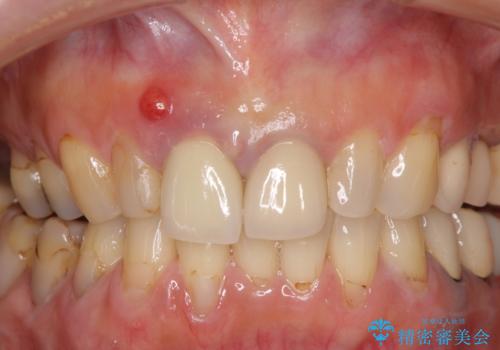

- 神経の抜いた歯が折れてしまい、痛みを感じて来院された患者様です。

折れてしまった歯は抜歯せざるを得ないため、抜歯と同時に仮歯を装着し、その後オールセラミックブリッジにて補綴することとしました。

折れた前歯を抜歯すると、歯肉が痩せてしまい、ブリッジの形態の審美性が失われることがあります。仮歯を調整することで審美回復が必要であるか判断しますが、今回は歯肉移植を行うことなく補綴治療を行いました。